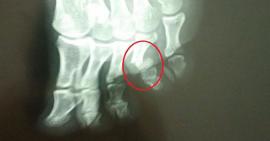

Hiểu biết sai lầm về gãy xương ngón chân mà người bệnh dễ mắc phải

Gãy xương ngón chân là một trong những chấn thương nguy hiểm về xương khớp, là tình trạng nứt hoặc vỡ xương trên các phần ngón của...